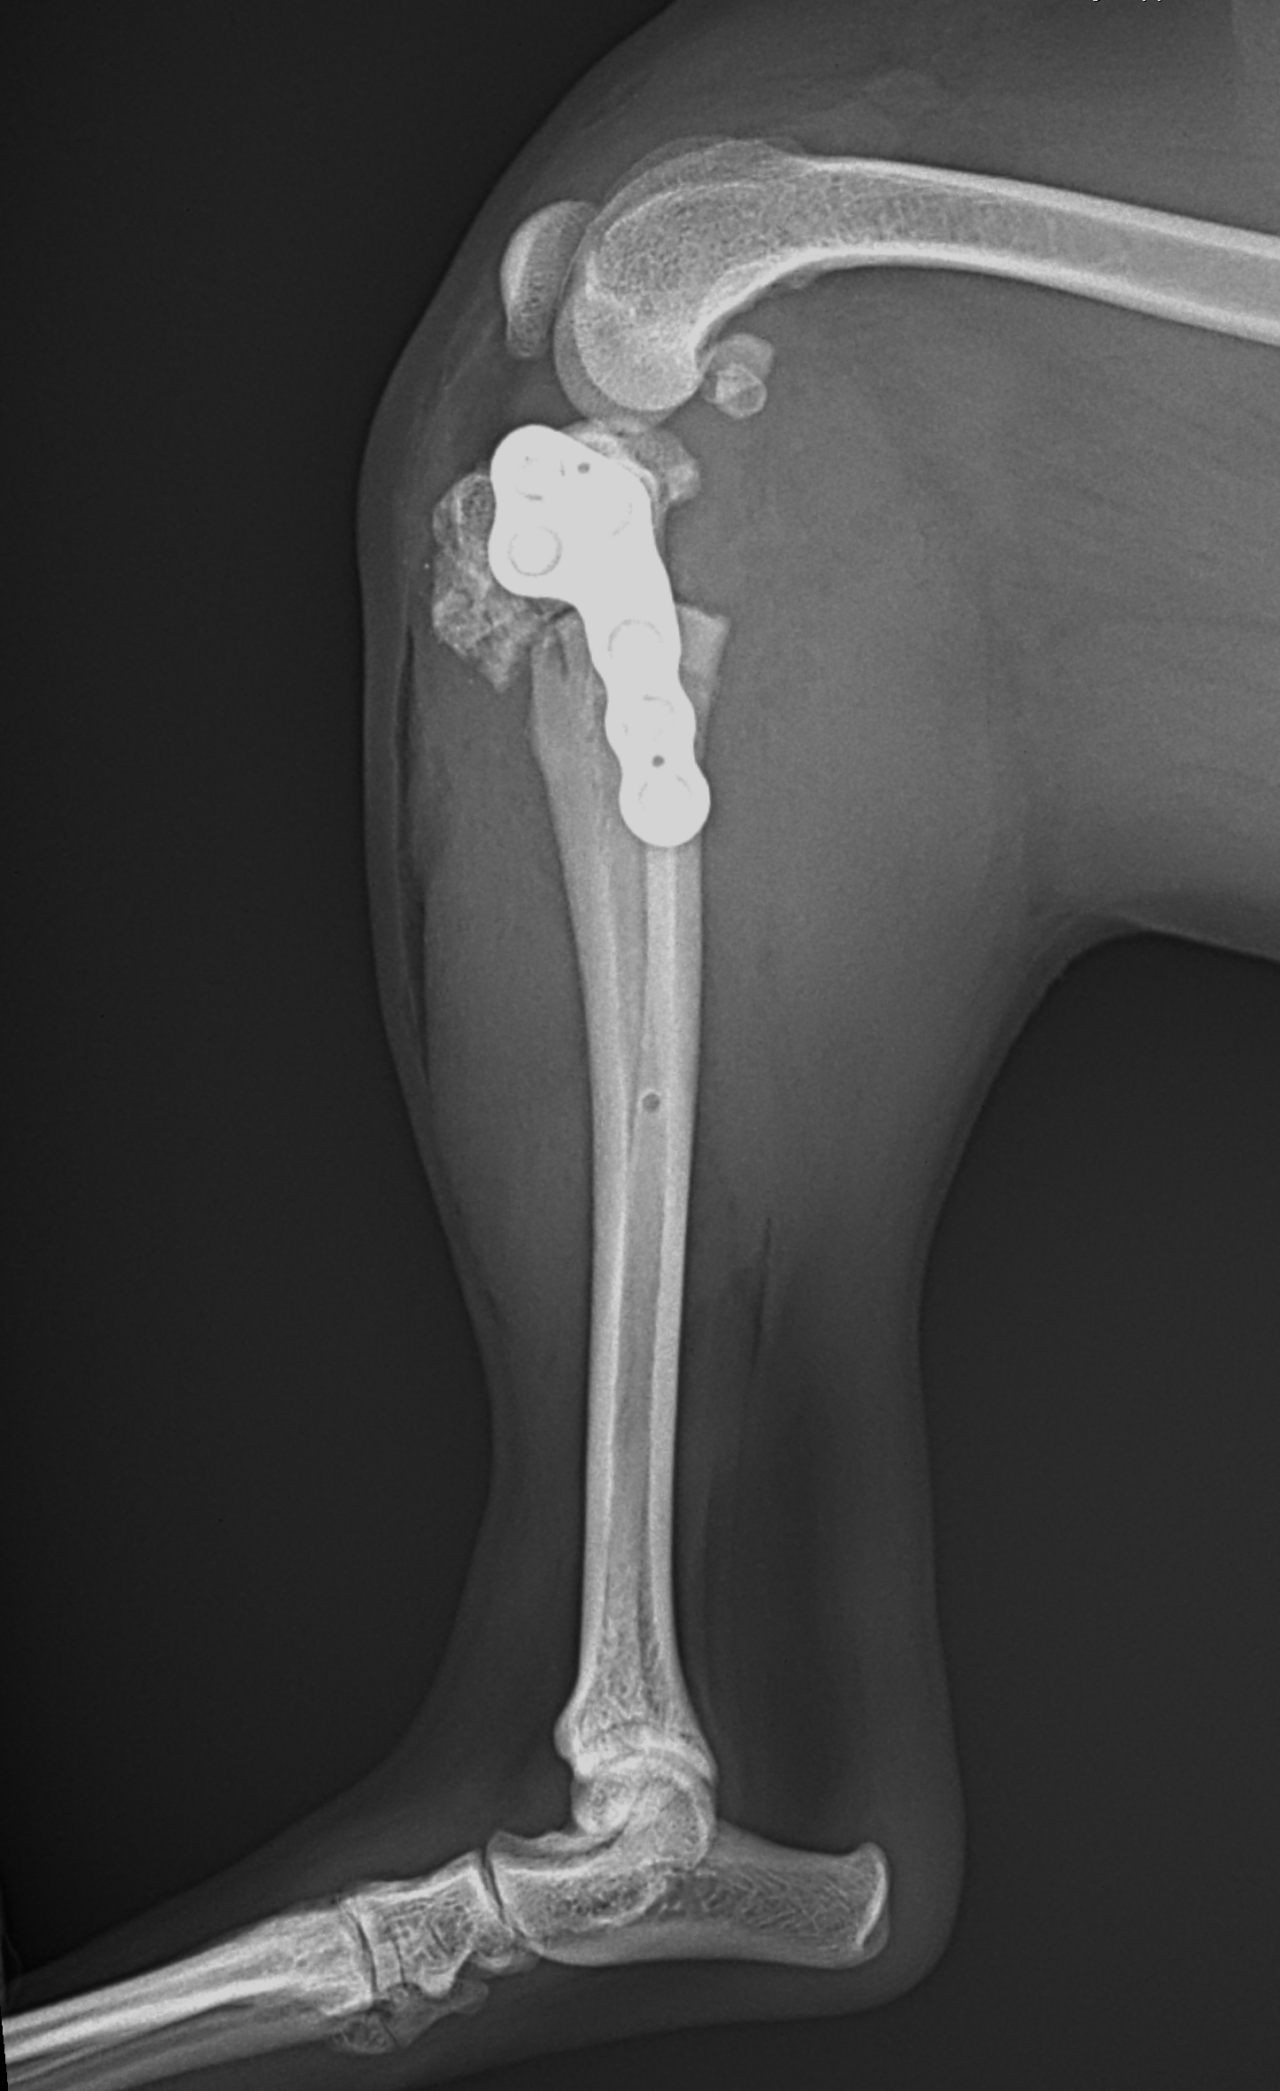

Toy Poodle×マルチーズのMix犬が前十字靭帯断裂により跛行が持続しているとのことでかかりつけ医より外科手術のために紹介来院されました。過去に膝蓋骨内方脱臼の手術を受けています。脛骨粗面移行術で使用されていたピンを除去したのち、CBLOで対応いたしました。しばらく安静が必要です。